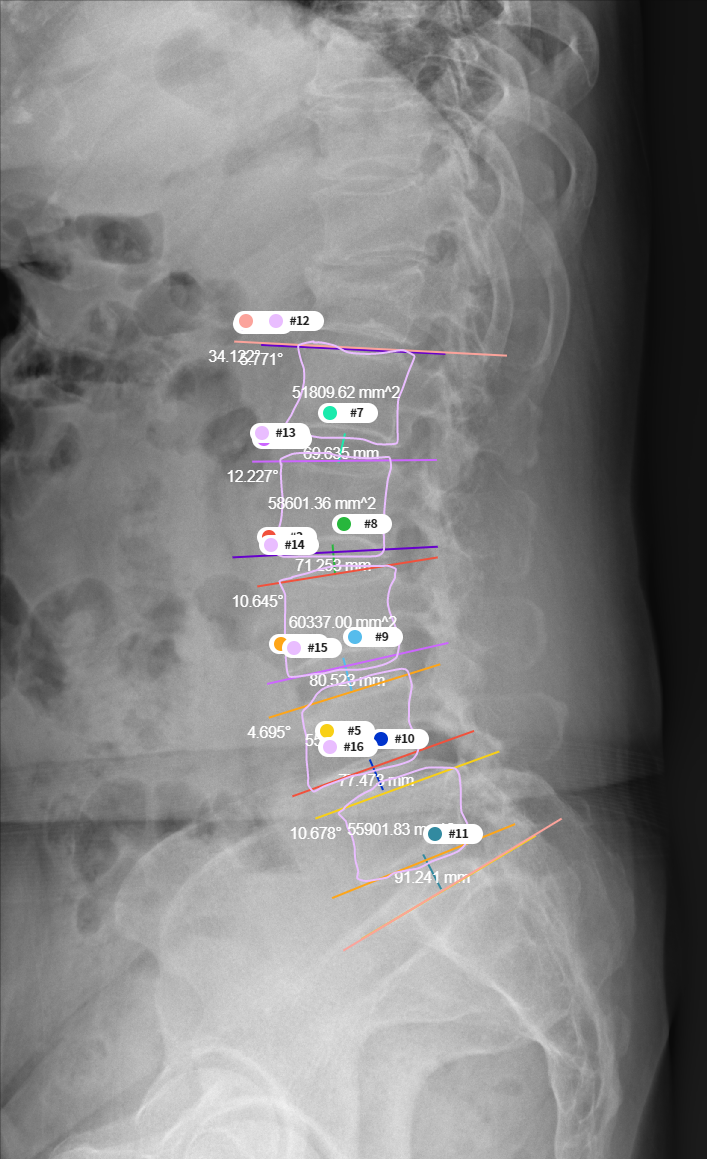

– Dice Coefficient Score 등데이터 비율 23776장 5944장 746장 - Predict 결과물의 각도와 거리 측정

- Predict mask 이미지의 외곽선을 추출하는 contour 기능을 이용하여 4번 5번 요추를 검출하고, 해당 데이터의 각도와 거리 측정

- 측정된 각도와 거리를 실제 측정값과 비교하여 Pearson-Correlation 분석

[요추 4, 5번 간의 디스크 높이 및 각도 측정]